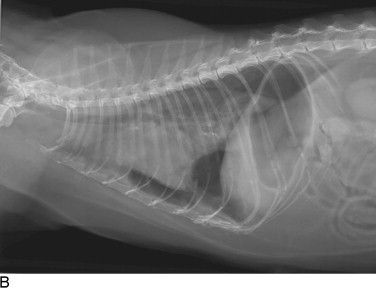

Thoracic radiographs are extremely helpful in diagnosing and quantifying pleural space disease and other intrathoracic pathology. Repeat radiographs after thoracentesis can be of diagnostic utility but were found to rarely be beneficial in providing additional diagnostic information in one human study.7 Routine radiographs after thoracentesis are considered unnecessary for stable patients in the absence of suspicion, clinical indication, or risk factors for complications (mostly pneumothorax)7,8 (Figure 30-1 ). Because the shape of the canine and feline chest is much different from that of humans, it is possible that dorsoventral radiographs in animals with pleural effusion (following thoracentesis) may still have improved diagnostic utility for evaluating the dorsal lung fields. Ultrasonographic examination is very helpful for rapid identification of pleural fluid in the emergency setting. In human medicine, indications for use of ultrasonographically guided thoracentesis include a small-volume effusion, inability to properly position the patient, failure of fluid to layer out on radiographs, and coagulopathy.9 “In veterinary medicine, ultrasound guidance is used routinely to confirm the ideal point of needle insertion for thoracentesis, mostly in patients with a small volume of effusion, fluid pockets or those at increased risk for complications.”

Figure 30-1.

Cats with pleural space disease. A, Moderate volume of malignant effusion secondary to bronchogenic adenocarcinoma. B, Pneumothorax after thoracentesis in the patient shown in A.C, Traumatic pneumothorax from high-rise syndrome. D, Spontaneous pneumothorax from diffuse pulmonary metastasis of salivary gland adenocarcinoma.